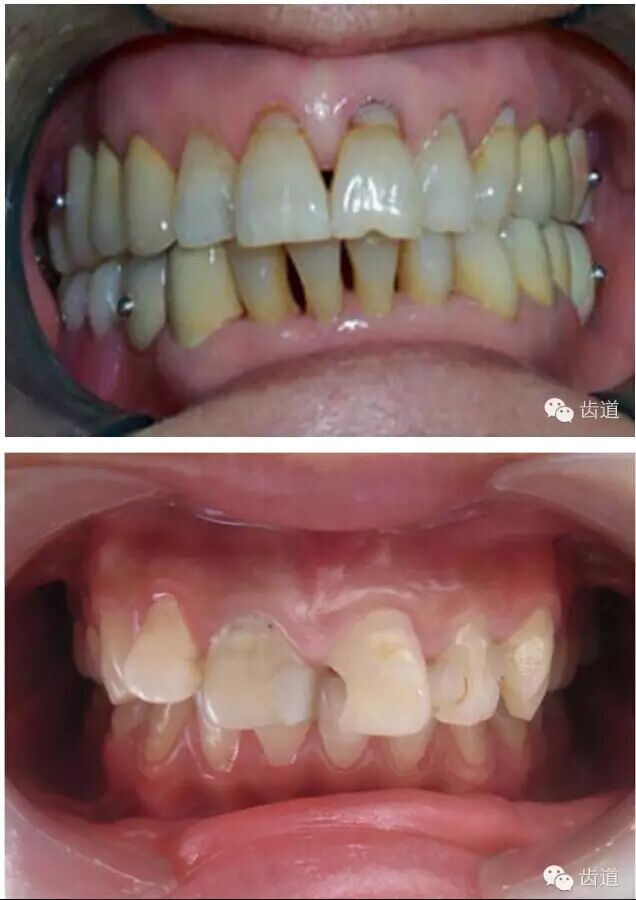

l基牙具有良好的固位形

l基牙具有良好的抗力形

l實際備牙產(chǎn)生的問題

l防止過度預備(造成牙髓激惹)

l保留活髓(保留牙體的整體性和韌性)

l過度預備抗力形喪失